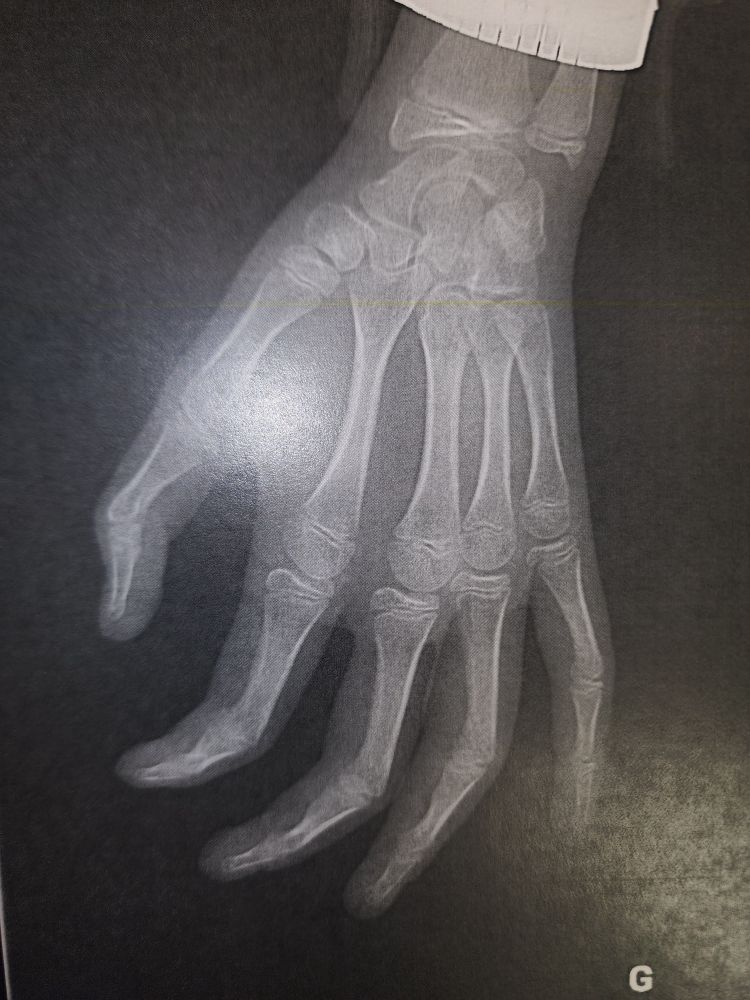

Petite question pour ma fille de 11 ans qui s'est fait une fracture il y a 2 jours au niveau de P2 du 4eme rayon equivalent à un Salter 3. Quelle attelle pour immobilisation svp? 🙏🙏🙏